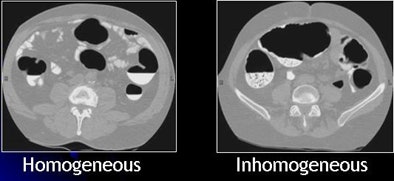

| Images show CTC data before and after electronic cleansing. All images courtesy of Hiro Yoshida, Ph.D. |

The general assumptions in EC development are that residual feces are fluid rather than solid, that tagging is homogeneous, and that bowel cleaning is rigorous, Yoshida said. But the reality is quite different. CTC exams come with widely divergent levels of quality in tagging and cleansing. A wide variety of bowel preparation techniques and agents are emerging for use in CTC, he said.

| Inhomogeneous tagging often appears in reduced or nonlaxative CTC. The uneven appearance of tagged materials on CTC data represents a mixture of semisolid fecal materials, air bubbles, fat, undigested foodstuffs, and unevenly distributed contrast agents. |

Inhomogeneous tagging often appears in reduced or nonlaxative CTC data, resulting from a mixture of semisolid fecal materials, air bubbles, fat, undigested foodstuffs, and unevenly distributed contrast agents.